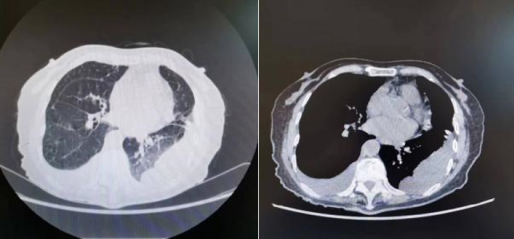

7月8日胸部CT ↑

从肺部HRCT可见双侧胸腔积液(左肺部分包裹性积液)伴邻近肺组织膨胀不全,对比2022年7月8日影像学发现:右侧胸腔引流管置入,新增右侧少许气胸,右侧胸腔积液较前减少,左侧胸腔积液较前增多;两肺散在条索影伴渗出较前进展;腹部较前变化不大,盆腔少量积液。2022年7月15日,患者再次行右侧胸腔闭式引流。